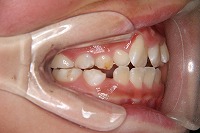

右 | ![]() |

![]() |

反対咬合を主訴に来院された、右側唇顎裂の10歳6ヵ月の女の子です。診断「右側唇顎口蓋裂で反対咬合を伴う」1期治療で反対咬合の解消と上顎の前歯の並びを修正しました。2期治療は抜歯をせず治療を行いました。